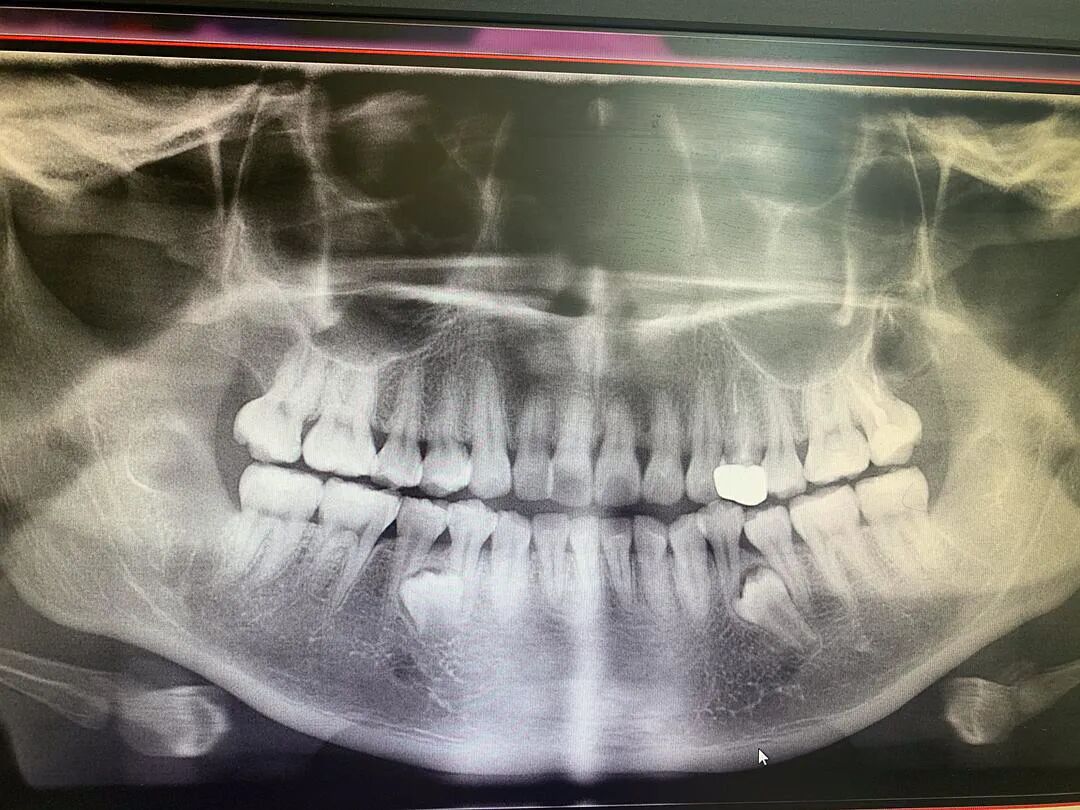

拔除之前

数量标记图

目前除了下面两颗埋伏牙,十二颗智齿全拔除干净了。